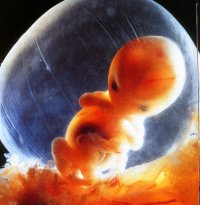

By eight weeks, the baby's arms and legs have grown longer, and the muscles have become evident.  The baby can feel and is actually capable of playing with the yoke sac.  The baby can spread its toes, move about and is very much alive.